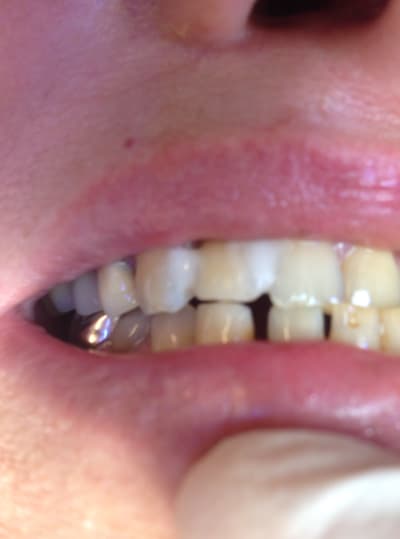

tu m'étonnes que la vis aies cassé 😊

Elle vient taper avec sa canine en plein sur sa latéral (2eme photo). Pas de dents En postérieur et articulé croisé.

ca on est d'accord mais Le gros problème c'est que le bord libre de son incisive vient buter contre la pointe canine ...

Donc avec des dents postérieures est ce que vous vous amuseriez à reposer une couronne sur cet Implant ou à reposer un implant - couronne ? Moi non